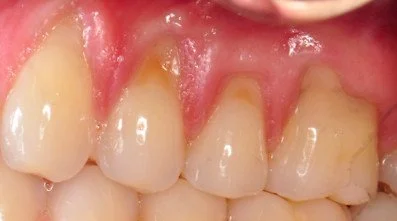

Close-up of teeth showing gingival recession on teeth #6 and #11.

Before